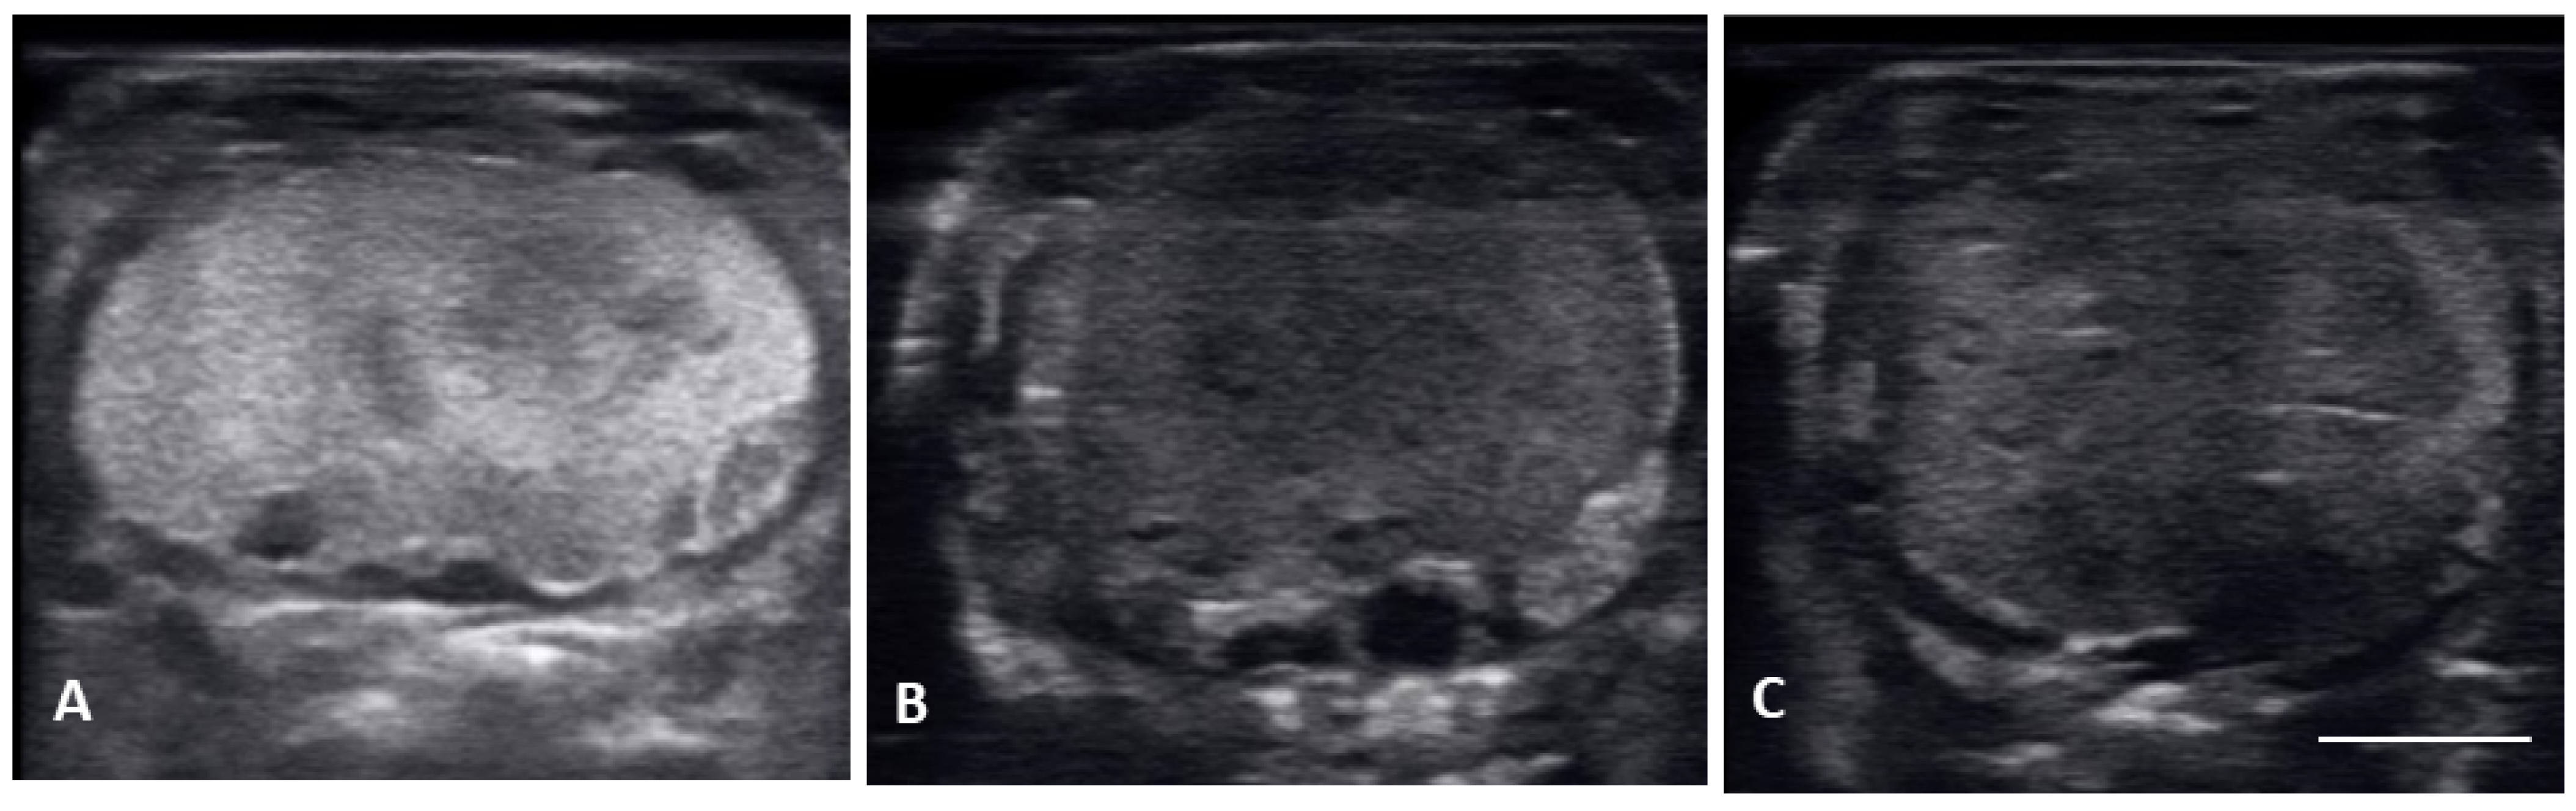

| Previtellogenic Follicles (PVF) | Anechoic Follicles, Small and Rounded, String-Aligned |

|---|---|

| Early vitellogenic follicles (EVF) | Small, round follicles showing hyperechoic outline around an anechoic middle and hyperechoic center. |

| Vitellogenic follicles (VF) | Oval shaped follicles showing a thickening hyperechoic outline as granulosa cell layer increase, hyperechoic ooplasm, and an anechoic core centrally located. |

| Preovulatory follicles (PrOV) | Elongating and increasing hyperechoic ooplasm as follicles are filled with yolk, with an elongated anechoic area located in the periphery of the ooplasm. |

| Peri-ovulatory follicles (PERI) | Elongated follicles, mostly homogenous hyperechoic structure with thick hypoechoic outline. Before female is overtly swollen. |

| Post ovulatory follicles (POV) | Ovulated follicles, passed into the oviduct showing an hypoechoic surrounding, but no visible calcified layer. |

| Shelled eggs (Shell) | Ovulated follicles, passed into the oviduct and surrounded by a calcified layer. |